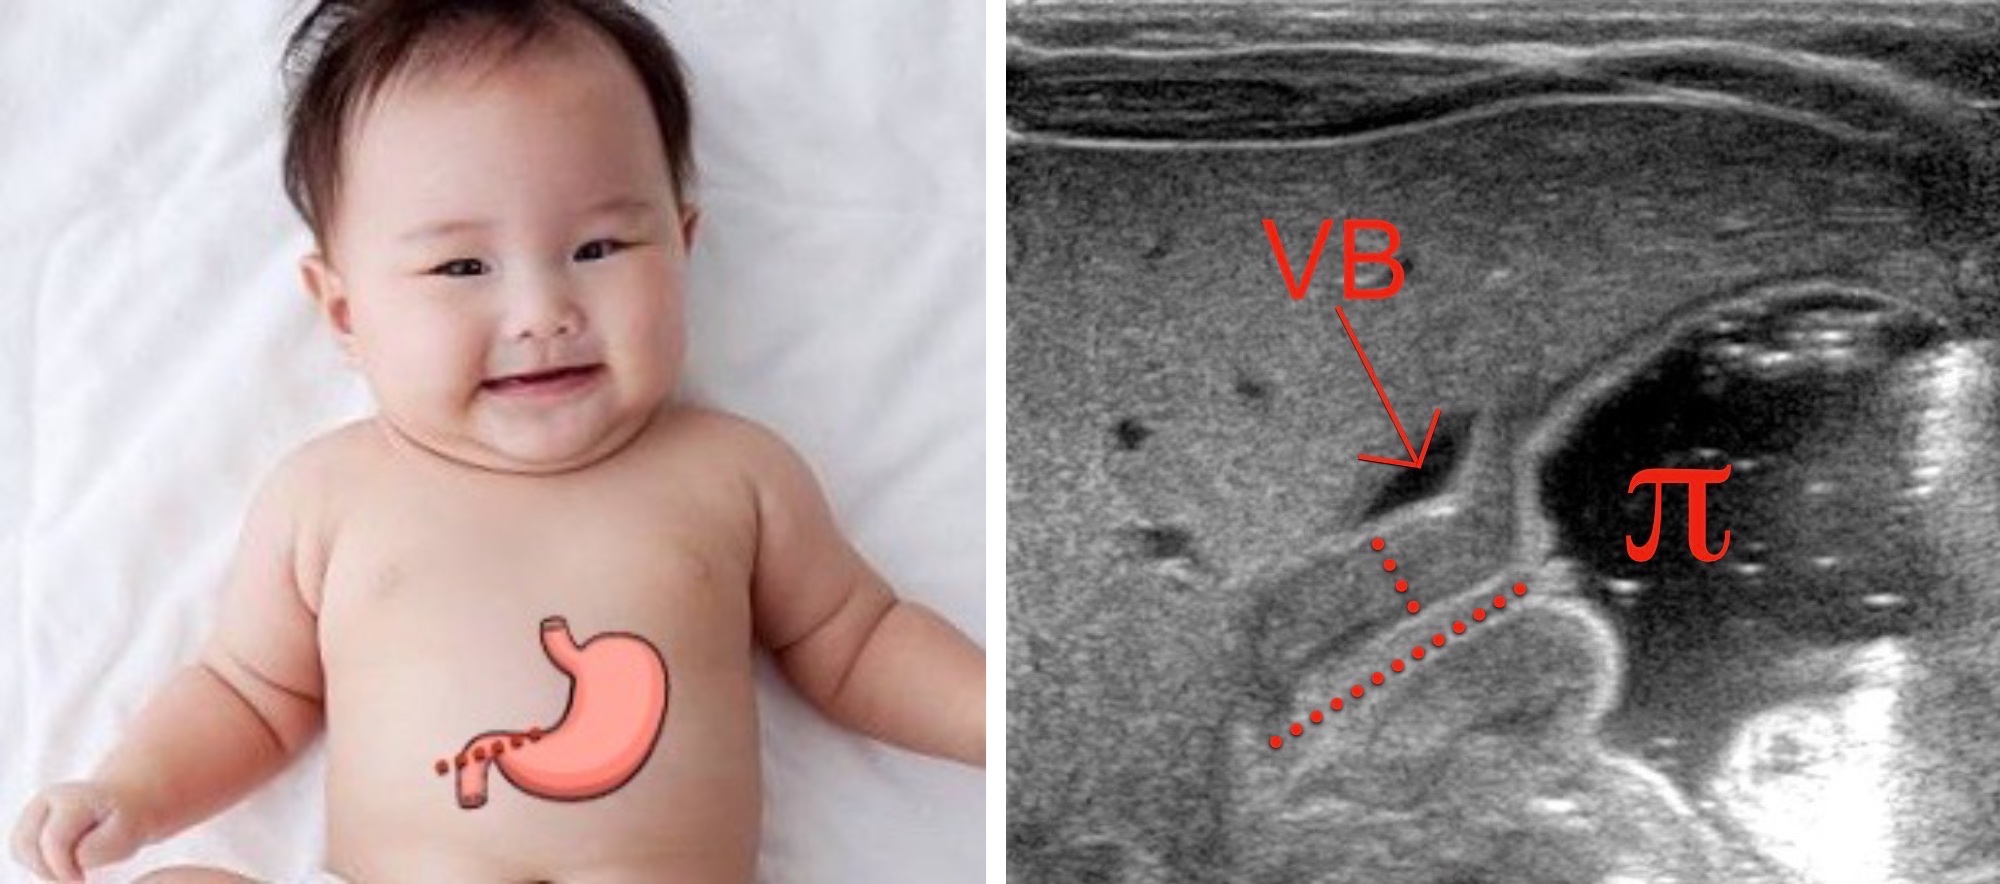

Aspect normal du pylore, avec grand axe < 14 mm et épaisseur de la musculeuse < 3 mm.

Intérêt d'un contrôle échographique en cas d'évolution défavorable.

- garçon M1-M3, vomis alimentaires en jet, musculeuse > 3 mm et L > 14 mm

- négatif => répéter écho à 24-48h = tourner vers la droite

Sténose hypertrophique du pylore

Sténose hypertrophique du pylore